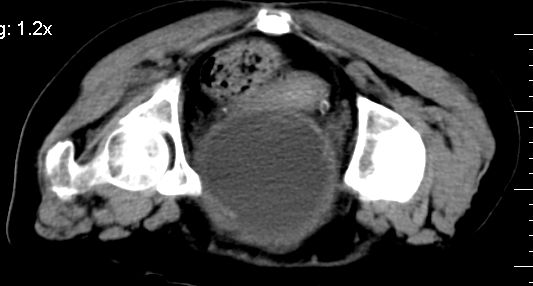

膀胱后壁见不规则致密影,我们遇到这样的病人都再做一次俯卧位扫描;排出膀胱内凝血块。

1.膀胱后壁见不规则致密影,占位?膀胱内凝血块?建议俯卧位扫描、膀胱镜检查.

2.双侧输尿管下段扩张.

1.膀胱后壁见不规则致密影,随体位改变,为膀胱内凝血块;

2.双侧输尿管下段扩张.输屎管结石可能大。建议作进一步检查。

2.双侧输尿管下段扩张.输屎管结石可能大。

2.双侧输尿管下段扩张,临床有血尿病史,建议进一步检查,找出血原因。